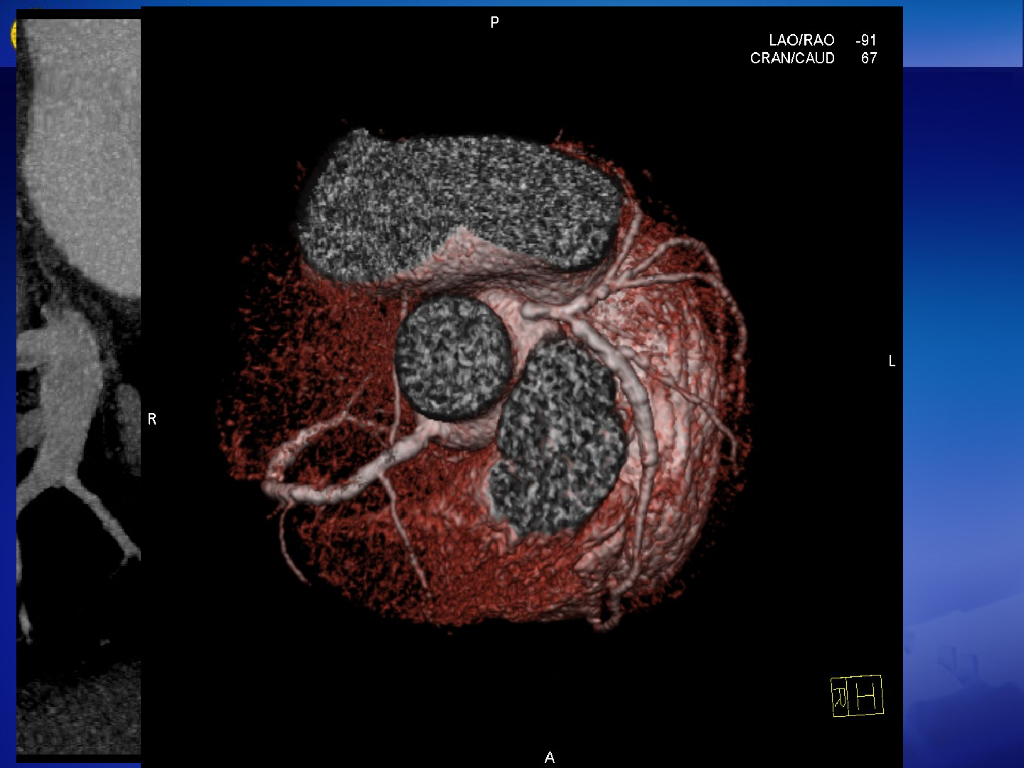

《放射诊断学》演示文稿-高心、肺心、冠心病--实习.pdf